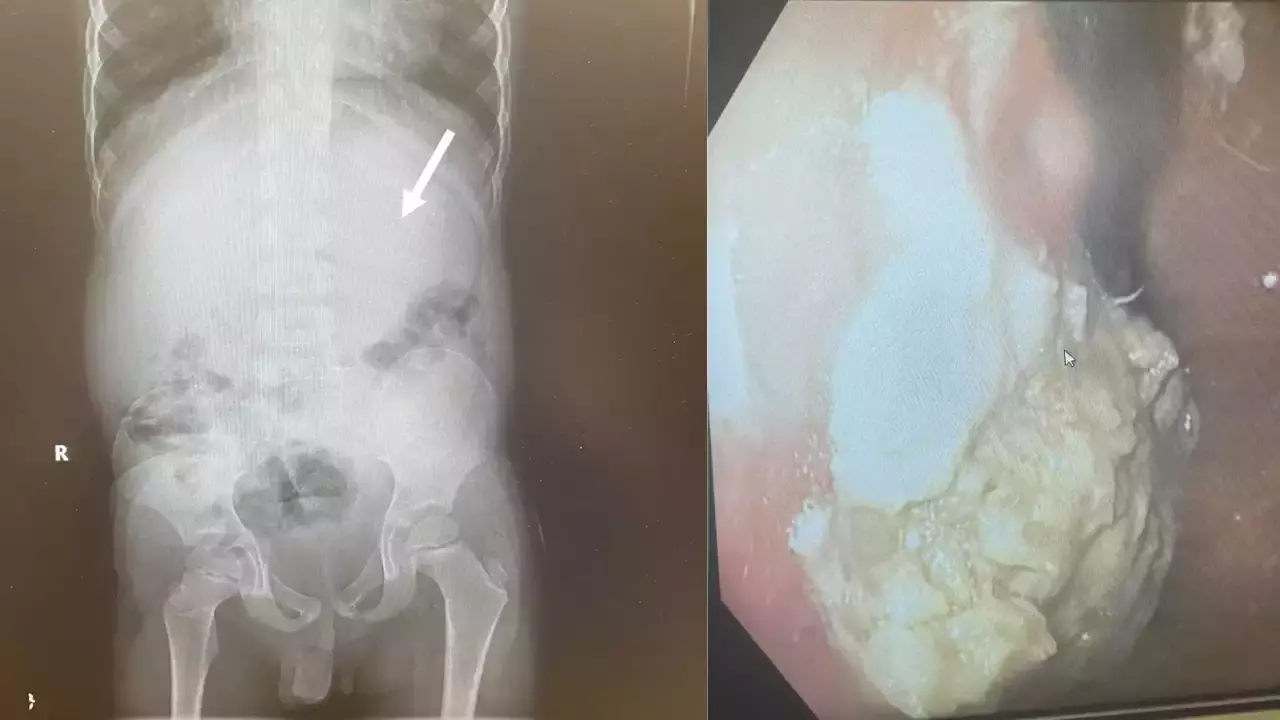

എന്‍ഡോസ്കോപിക് ചിത്രങ്ങള്‍

വാഷിംഗ്ടണ്‍: അമേരിക്കയിലെ ഒഹിയോയില്‍ 40 ച്യൂയിംഗ് ഗം വിഴുങ്ങിയ അഞ്ചു വയസുകാരന് അടിയന്തര ശസ്ത്രക്രിയ നടത്തി.കുട്ടിയുടെ ആമാശംയ ബ്ലോക്കായതിനെ തുടര്‍ന്നാണ് ശസ്ത്രക്രിയ നടത്തേണ്ടി വന്നതെന്ന് ഡോക്ടര്‍മാര്‍ പറഞ്ഞു. ച്യൂയിംഗ് ഗം കഴിച്ചതു മൂലം ദഹനവ്യവസ്ഥ തടസപ്പെട്ടിരുന്നു. വയറുവേദനയും വയറിളക്കവും ഉണ്ടായതിനെ തുടര്‍ന്നാണ് കുട്ടിയെ ആശുപത്രിയിലെത്തിച്ചത്.

ക്ലീവ്‌ലാൻഡ് ക്ലിനിക്കിലെ ഡോ. ചിസൈറ്റ് ഇഹിയോനുനെക്വുവിന്‍റെ നേതൃത്വത്തിലുള്ള സംഘമാണ് ശസ്ത്രക്രിയ നടത്തിയത്. ഫോഴ്‌സ്‌പ്സ് ഉപയോഗിച്ചാണ് ഡോക്ടർമാർ ഗം നീക്കം ചെയ്തത്.ച്യൂയിംഗ് ഗം ശരീരത്തിൽ ഏഴ് വർഷത്തോളം നിലനിൽക്കുമെന്ന മുന്നറിയിപ്പിനെ വിദഗ്ധര്‍ തള്ളിക്കളഞ്ഞു. “നിങ്ങൾ ഒരു കഷണം ഗം വിഴുങ്ങിയാൽ, അത് ഏകദേശം 40 മണിക്കൂർ കഴിഞ്ഞ് നിങ്ങളുടെ വിസര്‍ജ്യത്തിലൂടെ പുറത്തുവരും,” ഡയറ്റീഷ്യൻ ബെത്ത് സെർവോണി ക്ലീവ്‌ലാൻഡ് പറഞ്ഞു. എന്നാൽ പുതിന ഫ്രഷ് ച്യൂയിംഗ് ഗം കഴിക്കുന്നത് ശീലമാക്കരുതെന്നും ദഹിപ്പിക്കാൻ കഴിയാത്തതിനാൽ ഇത് കുടൽ അസ്വസ്ഥത ഉണ്ടാക്കുമെന്നും അദ്ദേഹം പറഞ്ഞു. “നിങ്ങൾ ഇത് എല്ലാ ദിവസവും അല്ലെങ്കിൽ ഒന്നിലധികം തവണ ചെയ്താൽ, ഇത് കുടൽ തടസ്സത്തിന് കാരണമാകും,” സെർവോണി മുന്നറിയിപ്പ് നൽകി.